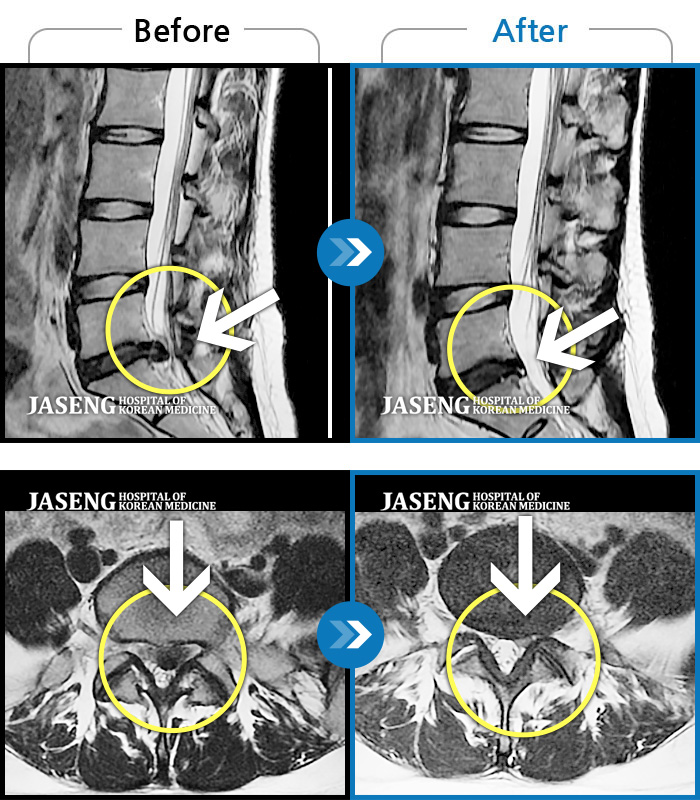

MRI 치료사례

보행 시 통증 및 좌측 다리 통증